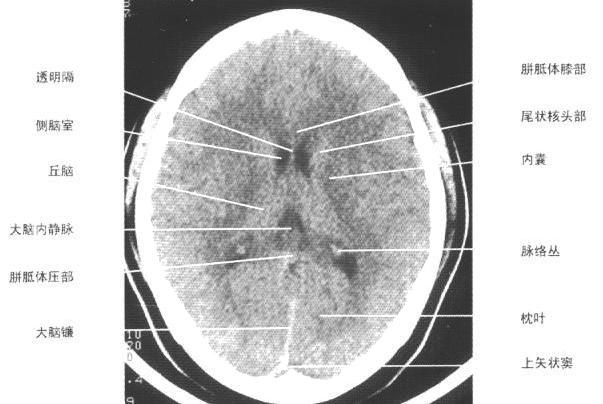

| 侧脑室体部层面